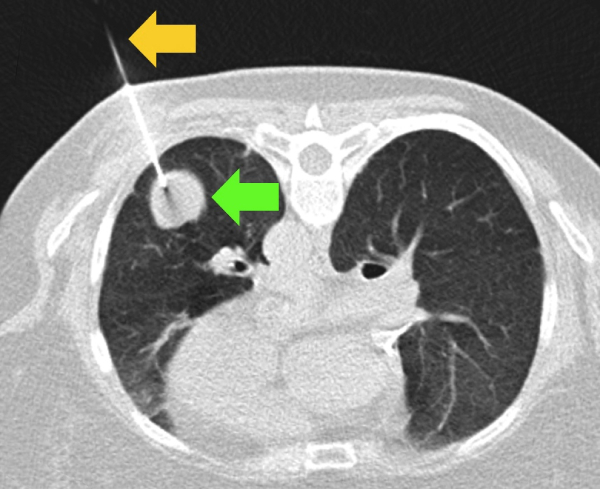

1. ปอด (Lung)

มะเร็งปอดครองแชมป์สาเหตุการเสียชีวิตอันดับต้นๆ ของโลก ข้อมูลจาก GLOBOCAN ระบุว่าผู้ป่วยกว่า 70% ถูกวินิจฉัยเมื่อเข้าสู่ระยะลุกลาม (ระยะ 3 หรือ 4) แล้ว

สาเหตุหลักมาจากการที่ปอดมีโครงสร้างซับซ้อนและถูกบดบังด้วยกระดูกซี่โครง การเอกซเรย์ปอด (X-ray) แบบธรรมดาจึงยากที่จะเห็นจุดเล็กๆ ที่มีขนาดต่ำกว่า 10 มิลลิเมตร การตรวจที่แม่นยำกว่าคือการทำ CT Scan แบบใช้รังสีต่ำ (Low-dose CT) ซึ่งช่วยลดอัตราการเสียชีวิตได้ดีกว่าเอกซเรย์ธรรมดาถึง 20%